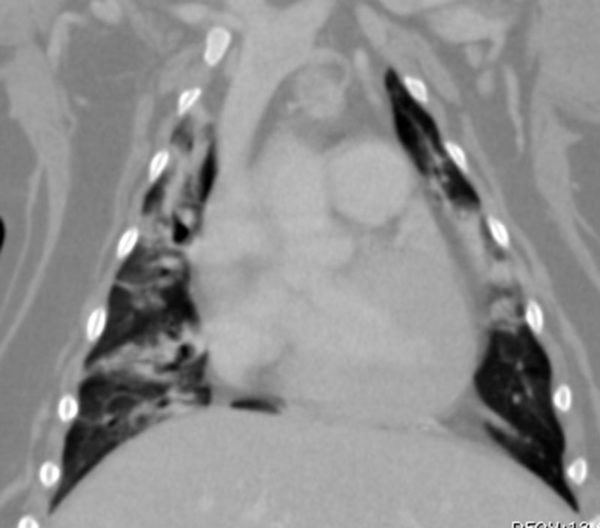

Computed tomography or CT of a dog chest.

Dog chest

CT imaging provides the UVTHS with high resolution cross sectional imaging of brain, spine, chest, abdominal and limb examinations.

CT imaging strength lies in its ability to image quickly for chest and abdominal studies so that images are not affected by the pet’s breathing. Exquisite bone detail is easily obtained for skull, sinuses, spine or limb studies.